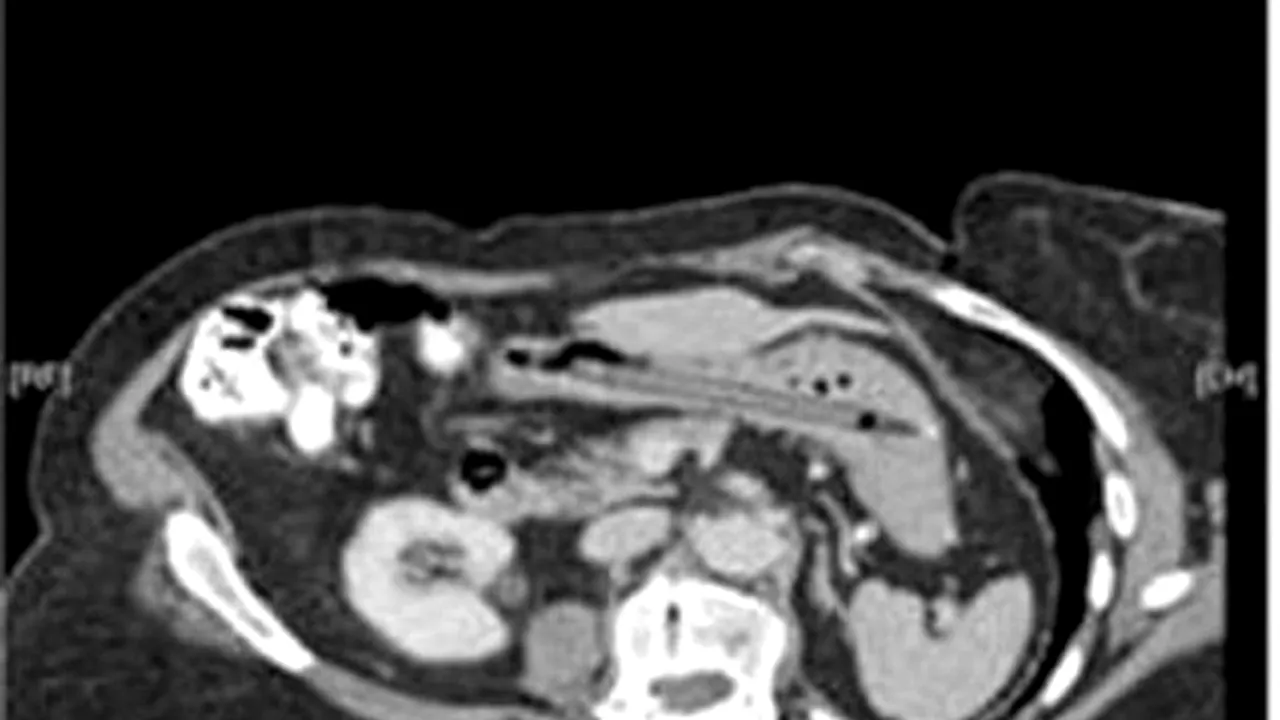

78 de tacâmuri

O femeie în vârstă de 52 de ani a înghițit toate tacâmurile din bucătărie. Margaret Daalman din Olanda i-a uimit pe medici. „Nu știu de ce am simțit nevoia să înghit toată vesela – nu m-am putut abține”, a spus Daalman.

Medicii au descoperit că femeia suferea de o tulburare de personalitate care o determina să „consume” tacâmurile din bucătărie. De fiecare dată când se așeza la masă, Daalman lăsa mâncarea deoparte și „mânca” tacâmurile. Totuși, aceasta a ingerat doar furculițe și linguri, lăsând cuțitele la locul lor. Femeia și-a revenit complet și a răspuns cu succes la un tratament pentru obsesia ei neobișnuită.